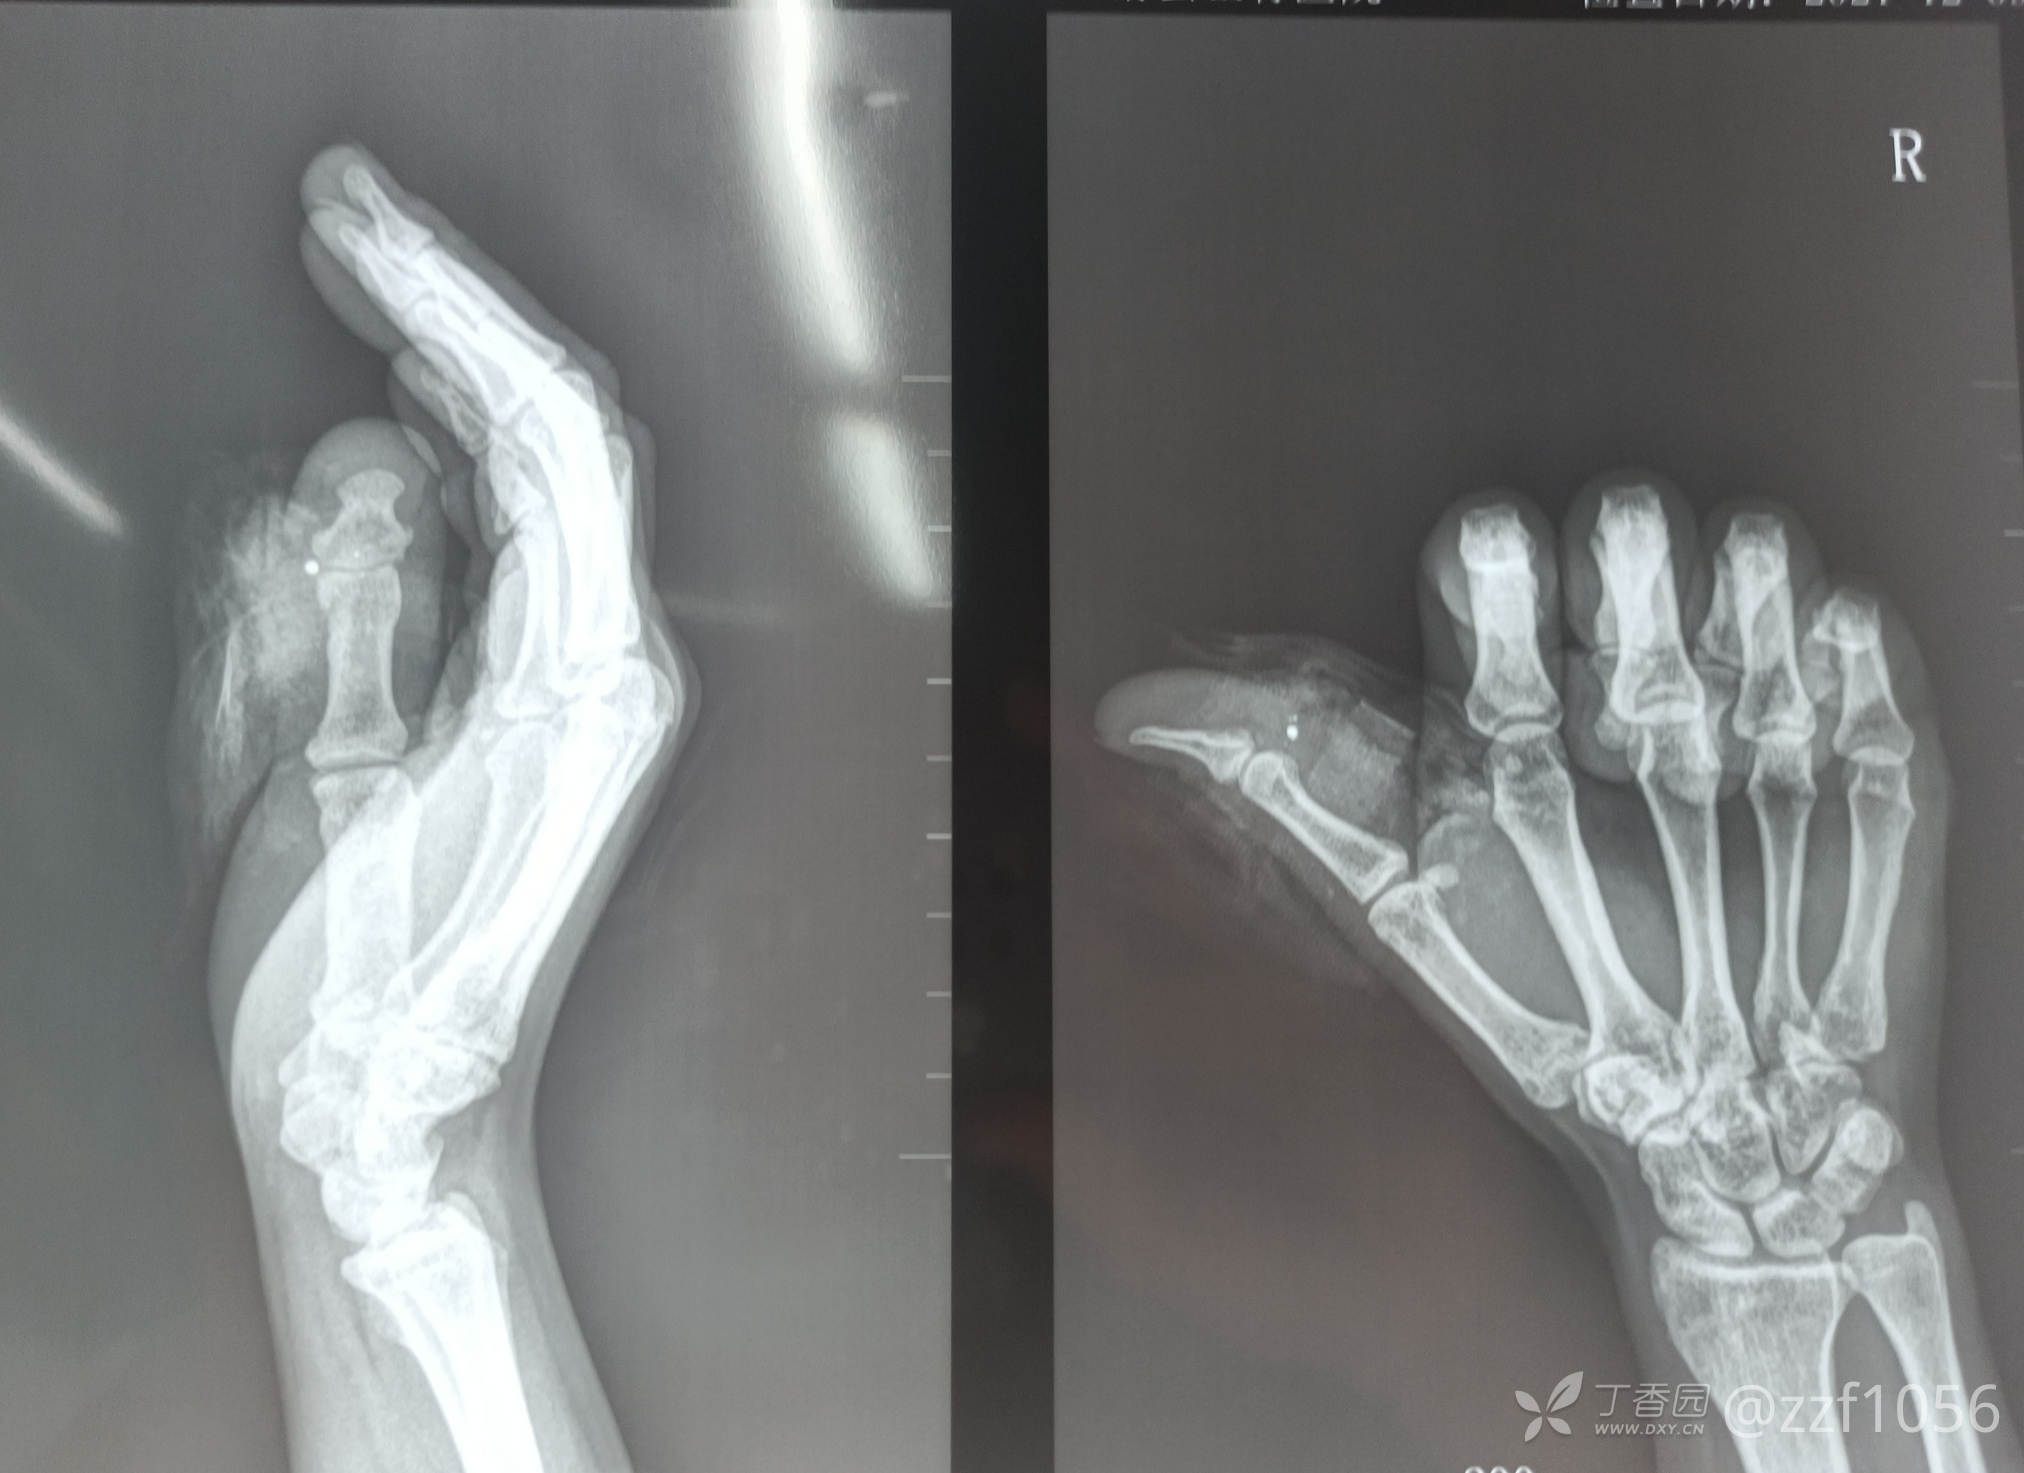

患者女,37岁,修路干活时三轮车挤伤右手拇指急诊来院,行急诊探查术

看着不重,出血不多,不仔细查体真不觉得很重,如果这方面不太专业话也许可能会清创缝合,因为偶有碰到这类情况

有经验的资深点的手外科医生或许一眼就能估计到损伤了哪些重要组织

果不其然,污染重,桡侧指固有动脉指神经屈肌腱止点缺损离断,仔细耐心一点,全部需要修复,为病人也好也为我带的年轻医生做个学习榜样